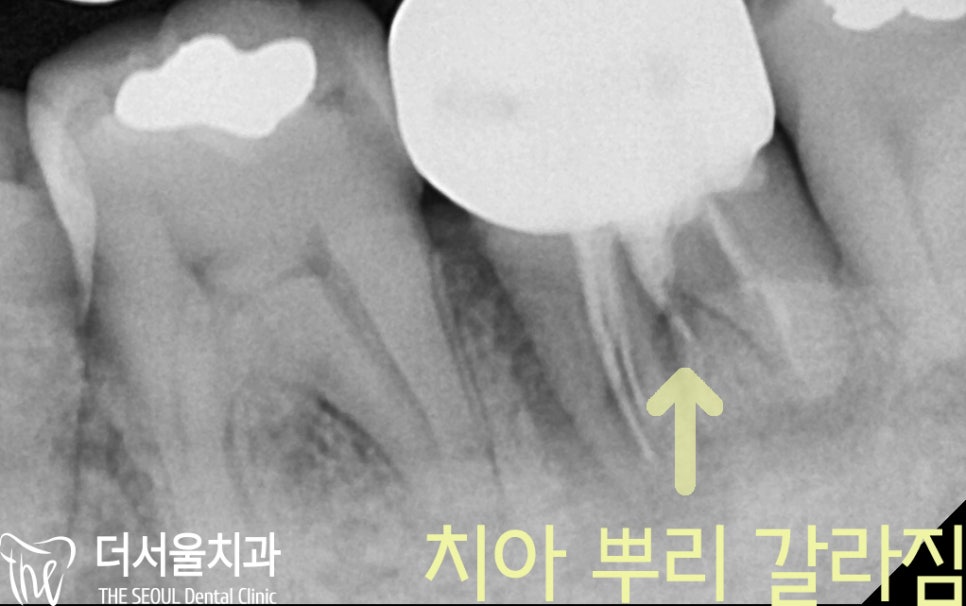

앞서 말한 부위를

치근단 촬영으로 확대해서 살펴봤더니

치아 뿌리가 갈라진 것을 확인해 볼 수 있었습니다.